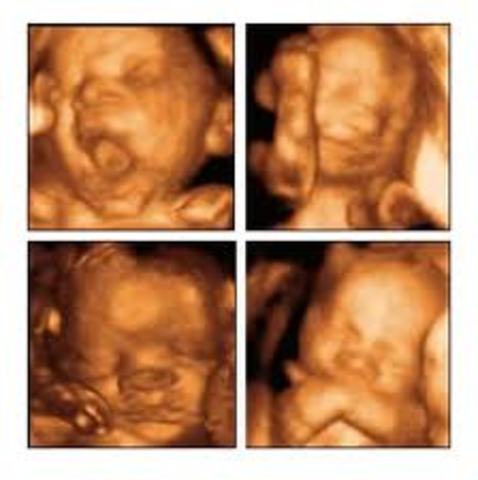

El feto se comunica Desde el vientre

La madre y el hijo se comunican , su madre por medio de la voz , y el feto por medio de los movimentos.